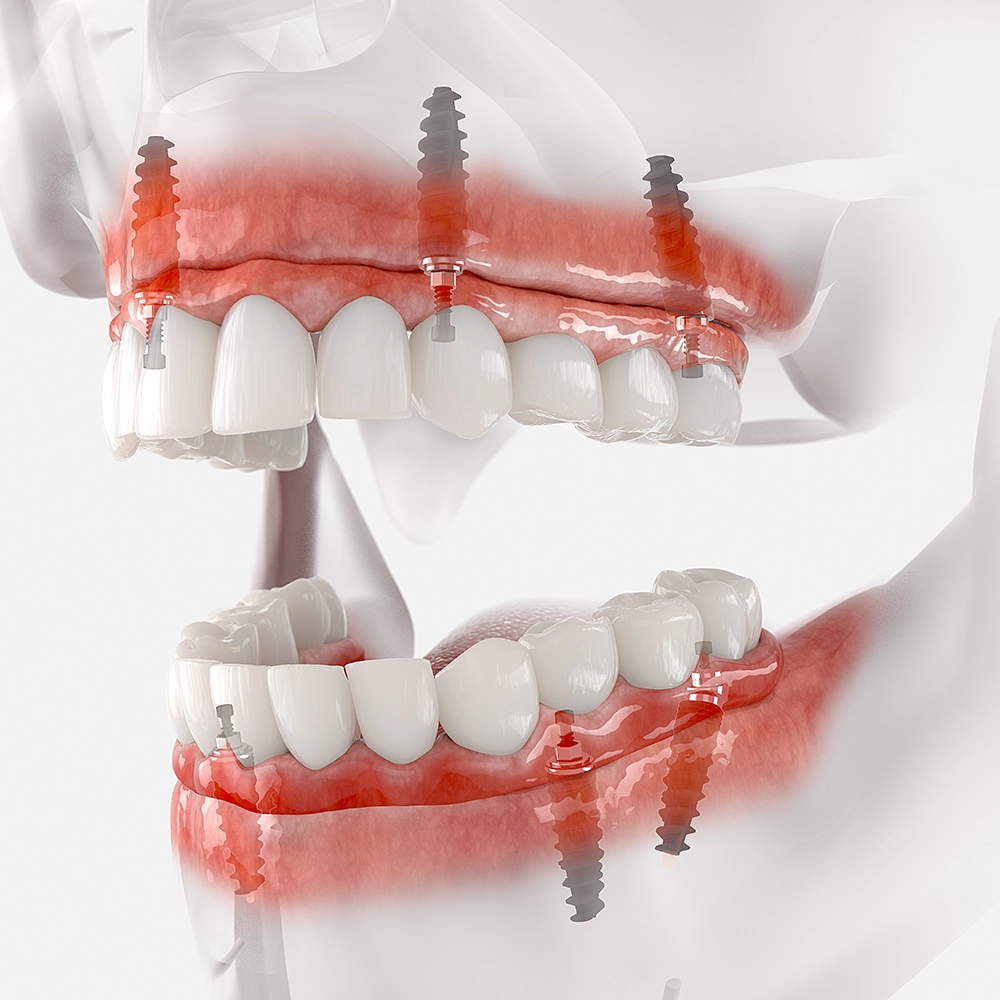

3D illustration showing a top and bottom set of implant-supported dentures in a transparent jaw model, highlighting the placement and structure of the implants within the gums.

Aftercare and Adjustment

Dentures, like all dental solutions, require care and occasional adjustments. As you adapt to your new set, we're here to make any necessary tweaks, ensuring they function efficiently and feel natural. We also offer guidance on cleaning and maintaining your dentures, helping them last longer and look pristine.